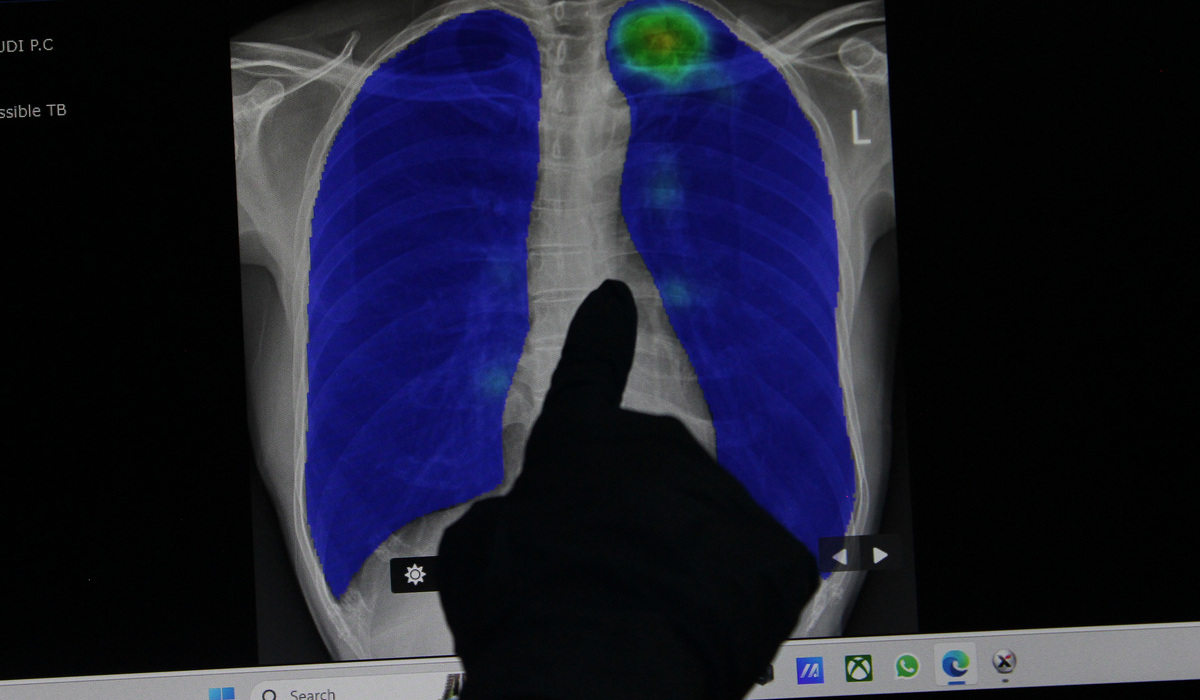

DIREKTUR Pencegahan dan Pengendalian Penyakit Menular Kementerian Kesehatan (Kemenkes) Imran Pambudi menyebut estimasi beban kasus Tuberkulosis (TB) di Indonesia sampai 1 juta kasus.

"Mengalami peningkatan dari semula sekitar 969 ribu kasus menjadi 1.060.000 kasus per tahunnya. Hal ini merupakan dampak dari penurunan penemuan kasus TBC di tahun 2020 dan 2021, dikarenakan adanya pandemi covid-19, yang kemudian berakibat penularan TBC ke orang di sekitar pasien TBC yang belum diobati," kata Imran kepada Media Indonesia, Jumat (2/2).

Dengan berbagai upaya yang terus dilakukan, sejak 2022 hingga saat ini, capaian penemuan kasus TBC terus meningkat dikarenakan penemuan dan pelaporan kasus TB serta pelacakan kontak TB mulai berjalan optimal.

Dokter spesialis Paru Erlina Burhan mengatakan kemajuan teknologi seharusnya mampu dapat mengeliminasi tuberkulosis. Namun hal itu juga perlu didukung dengan adanya kebijakan dari pemerintah untuk mengupayakan eliminasi TB.

"Kemajuan teknologi di bidang TB yang paduan pengobatannya dari 6 bulan menjadi 4 bulan untuk TB sensitif obat, sementara TBC-RO yang tadinya 18 bulan bahkan 2 tahun sekarang ada paduan terbaru BPaL dan BPaLM yang pengobatannya hanya 6 bulan saja," jelas Erlina.